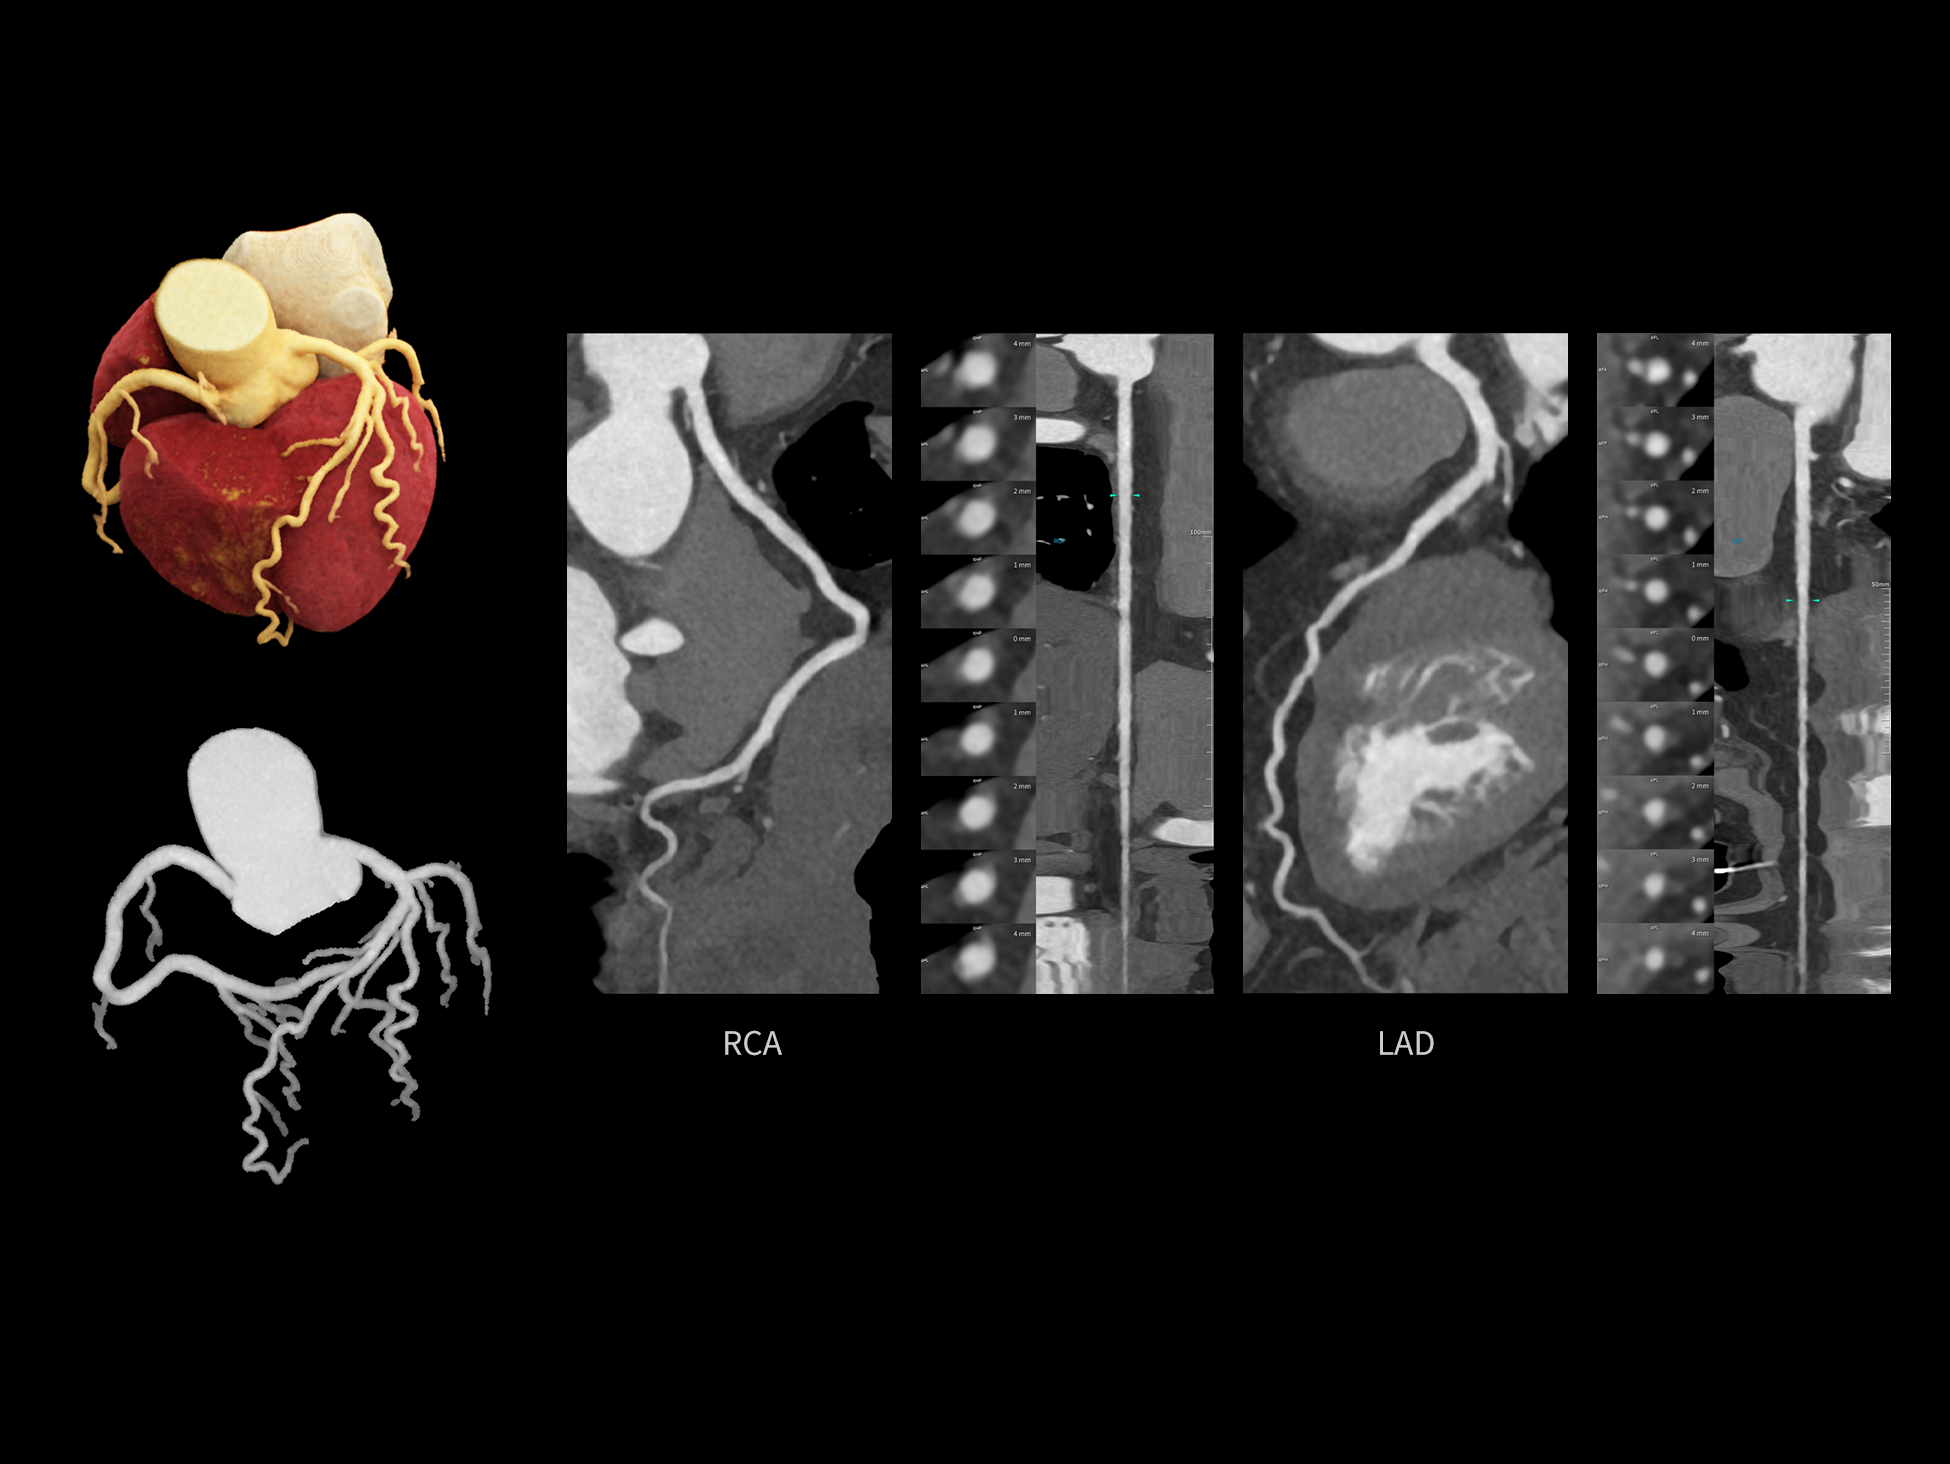

CardioCapture 2.0 通过“识别–追踪–建模–校正”的完整流程,精准分割心脏结构,动态追踪运动轨迹,并构建多时相运动场,最终实现冠脉、瓣膜、心肌及心室结构的同步校正,清晰洞见每一次心跳细微变化,真正将心脏动态掌握于毫秒之间。

CardioCapture 2.0 在目标时相前后重建多时相影像,通过深度学习网络精准提取冠脉中心线,进而建立时相间运动模型,实现对冠脉分段图像的精准运动校正。

CardioCapture 2.0 可对心肌、瓣膜及心室等结构进行同步运动校正。基于深度学习的心脏精细分割,实现了更完整的心脏全局信息提取,能有效抑制全心运动伪影,显著提升心脏细节的清晰度与诊断可靠性。

8ms 全心等效时间分辨率

冠脉运动校正

全心结构运动校正